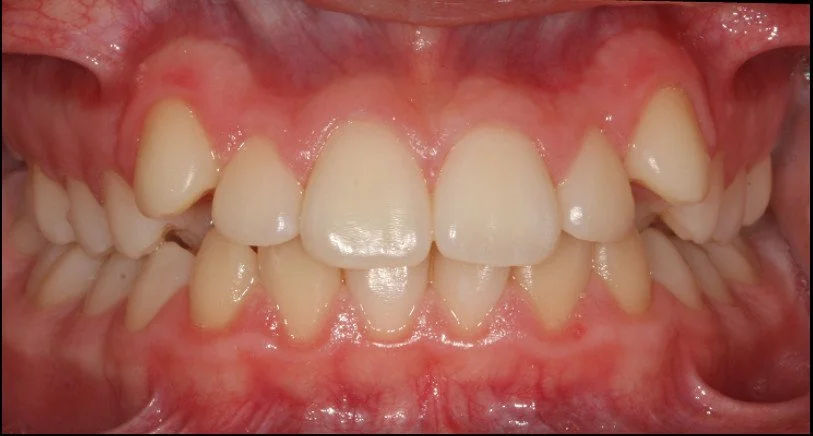

ORTODONZIA INTERCETTIVA + ALLINEAMENTO

BEFORE

AFTER

Caso di una paziente con morso aperto iniziale e palato stretto, trattato in giovane età con terapia intercettiva mediante espansione rapida del palato. Successivamente, in adolescenza, è stata sottoposta a trattamento ortodontico fisso in dentatura permanente.